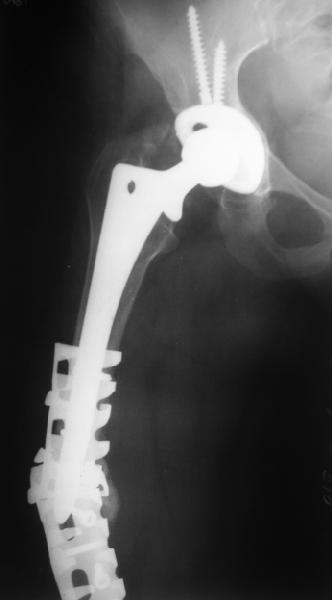

Female, rheumatoid, THA in 2003, car accident in 2006, failed plating. Nailing in Oct 2007. The nail is solid with hollow proximal part where the stem is docked. Last images are in 1 year after

nailing.

The femur responded by failure to Mennen plating (DePuy Bridge plate). So i would add that the ability to unite is realized in mechanically and biologically sound conditions.